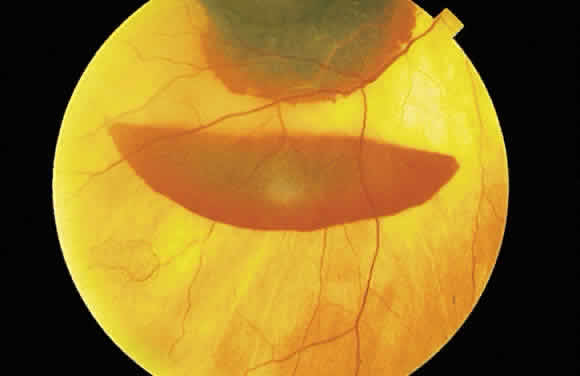

A hemorrhage in the nerve fiber layer (Fig. 11A) dissects along the plane of the layer parallel to the orientation of the internal limiting membrane (see Fig. 11B). A hemorrhage located between the retinal pigment epithelium and Bruch's membrane also spreads in a plane parallel to the orientation of the membrane (Fig. 12). However, its extent is limited by the adhesion of the pigment epithelium to Bruch's membrane, in contrast to a nerve fiber layer hemorrhage, where no such delineating structure is present. Therefore, a fresh nerve fiber layer hemorrhage appears bright red and has feathery borders, whereas a subpigment epithelial hemorrhage appears brown-black and has sharp borders (Fig. 13).

The location of the hemorrhage also may affect is ophthalmoscopic appearance. Fresh hemorrhage between the retinal pigment epithelium and Bruch's membrane may appear brown or red-black, in contrast with the bright red color seen in fresh hemorrhages anterior to the pigment epithelium (see Fig. 13A). The location of hemorrhages within the retina also accounts for the shape of the lesion. Blood that accumulates between the nerve fiber layer and the internal limiting membrane (subinternal limiting membrane hemorrhage) (Fig. 57) assumes a shape defined by gravity, meniscus or boat-shaped, when the patient is upright (Fig. 58). The name subinternal limiting membrane hemorrhage is technically ambiguous, since a hemorrhage in the outer plexiform layer also is below (sub) the internal limiting membrane.

Fig. 58. Hemorrhage located just beneath the internal limiting membrane with the patient in the upright position. The retinal vessels are visible on the surface of the layered hemorrhage.